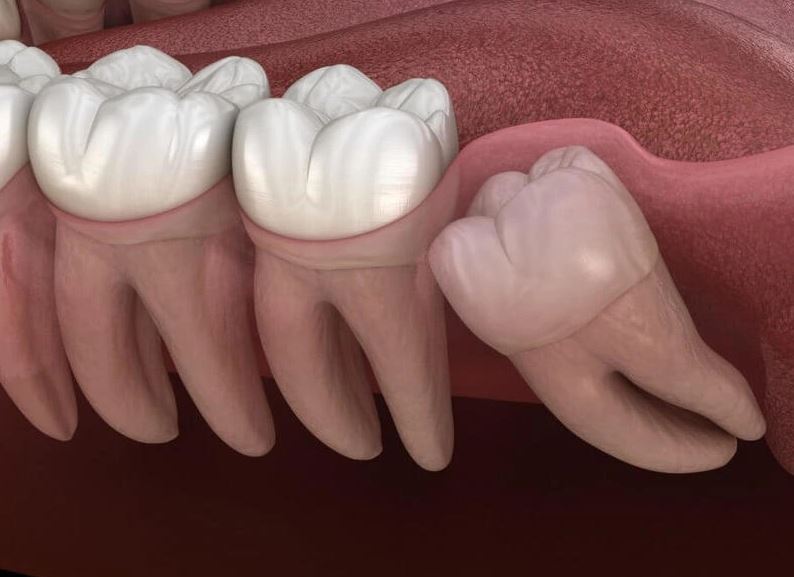

Nhổ răng số 8 mọc ngầm (Phổ biến nhất): Đây là giải pháp triệt để và được khuyến nghị nhất cho hầu hết các trường hợp răng 8 mọc ngầm gây biến chứng hoặc có nguy cơ gây biến chứng.

Quy trình nhổ răng khôn mọc ngầm hiện nay đã được cải tiến rất nhiều:

• Áp dụng công nghệ hiện đại: Việc sử dụng các công nghệ như máy Piezotome (máy nhổ răng siêu âm) giúp việc nhổ răng trở nên nhẹ nhàng, ít đau, ít sang chấn và thời gian hồi phục nhanh hơn.

• Phẫu thuật: Với răng ngầm sâu, bác sĩ thực hiện tiểu phẫu nhẹ nhàng để lấy răng.